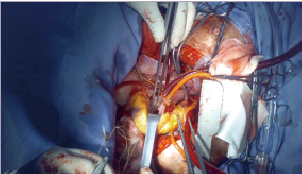

近日,国际心肺移植学会(ISHLT)更新了心脏移植标准。相较于2006版指南,新指南修改了某些心脏移植标准,并根据新证据放宽了推荐要求。(J Heart Lung Transplant. 2016,35:1)

哈佛大学医学院Mandeep R. Mehra教授表示,此次指南解答了很多争议性问题,如以往不适合进行心脏移植的情况(HIV、肝炎淀粉样病变、部分先心病),现在允许进行心脏移植。2006版指南不推荐对患者移植的年龄设限,也没有对既往癌症患者的移植时间进行限制(如癌症治愈至少5年),新指南不仅对这些问题都进行了更新,而且解决了当前最受争议的话题。

新指南主要变化

☆对于超重的心衰患者,新标准要求医生推荐减重项目,将患者体质指数(BMI)降至<35 kg/m2,而非先前是30 kg/m2。放宽BMI目标是基于新的循证证据,可让更多患者获得移植的机会。

☆由于新证据对心衰生存评分(HFSS)的预测准确性提出质疑,ISHLT建议,只有在预后不确定的情况下,才使用HFSS评估。

☆建议所有等待心脏移植的成年患者定期进行右心导管检查,直至移植之日。不推荐儿童患者常规进行定期右心导管检查。

☆对于存在潜在可逆或可治疗合并症(如癌症、肥胖、肾功能衰竭、吸烟、药物治疗不可逆性肺动脉高压)的患者,考虑机械循环支持,然后重新评估是否适合心脏移植。

☆任何在门诊中无法获得充分社会支持的患者,被视为移植的相对禁忌。严重的认知-行为障碍或痴呆患者(如自残、无法理解和配合治疗),心脏移植的获益尚未明确,甚至可能有害,因此不推荐这些患者进行心脏移植。

☆HIV感染、肝炎、查加斯病甚至结核病患者,如果治疗团队能严格遵守管理原则,可考虑进行心脏移植。